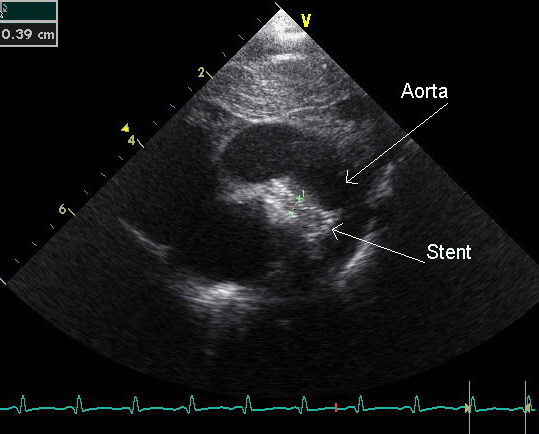

Coarctation of the Aorta

Coarctation of the aorta results in an abnormal narrowed portion of the aorta.

Coarctation of the aorta is separated into juvenile and adult versions.

Juvenile version of coarctation of the aorta

A patent ductus arteriosus (PDA), infantile form is connected.

Coarctation is located distal (after) to the aortic arch and proximally (before) to the patent ductus arteriosus (PDA).

Coarctation of the aorta presents in babies as lower extremity cyanosis, mostly after birth.

Coarctation of the aorta is linked to Turner syndrome (monosomy X).

Adult version of coarctation of the aorta

A patent ductus arteriosus (PDA) is not connected to adult form of coartctation of the aorta.

After (distal to) the aortic arch is where the coarctation is typically located in adults.

Coarctation of the aorta in adults typically presents with:

- Hypertension in the upper extremities

- Hypotension with weak pulses in the lower limbs

Radiology of coarctation of the aorta classically shows “notched ribs” on an x-ray due to collateral vessels.

Coarctation of the aorta is linked with the bicuspid aortic valve.